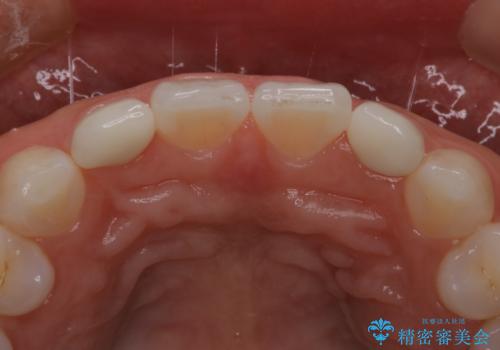

色や形をこだわりたいということで、当院最上位ランクのエクセレントにて治療を行いました。

当院で患者様の口腔内の写真を撮影し技工士さんに指示を出して完成します。

患者様はかなり喜ばれておりました。